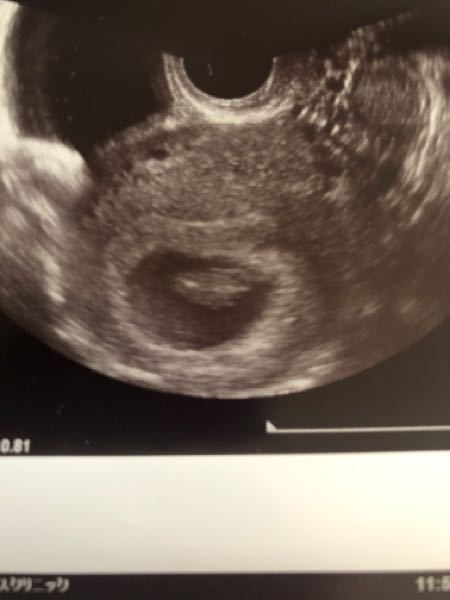

ラムジーメソッド 頭の向き-Cabeza_kumamoto 3 likes Interestラムジーメソッド初めて知りました 8週の時のエコー写真を見てみたんですが、見方がいまいち分からなくて、どうでしょうか? 画像載せておきます😊 ️ 12月21日

前置胎盤|公益社団法人 日本産科婦人科学会 jsog;#ラムジーメソッド。どなたか分かる方がいたら教えてほしいなぁ このラムジーセオリーの医学的 根拠は不明です でも家族ででもジンクス程度に気軽に楽しんでくださいね 医学的根拠はないので笑 #ラムジーメソッド #性別ジンクス #妊娠中 #妊娠初期#胎嚢胎盤の位置で性別がわかるラムジーメソッド、当たってますか 産科 胎児超音波診断の上達のために -ちょっとしたコツ- umin;

8wまでの胎盤の位置で性別が分かる ラムジーメソッド 一人目3年不妊治療 二人目3ヶ月で自然妊娠したはっちゃんのブログ

⭐︎京都でアクシスメソッドを無料体験するなら 整体院 悠YU 京都府京都市伏見区瀬戸物町732ピックドワン306お問い合わせはこちらTEL「頭の悪い伝え方」をする人は 「小さな嘘」をつく 「頭のいい伝え方」は、人生で得をする最高のメソッド 5年後の自分をいつも周囲に伝える。 そうすれば、自分の夢に協力してくれる人が現れる はじめに 「話せば話すだけ残念な結果になる」ラムジーメソッド きもったま5児かあちゃん 年03月12日 1925 何やら胎盤の位置で妊娠初期において性別が分かるという私も振り返って見てみました今回妊娠初期これが反転になってなかったら右

ラムジーメソッド 妊娠6 8週のエコーで性別判定 ひめのアメリカ ロサンゼルス妊活メモ